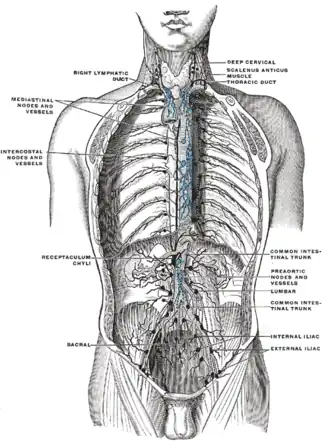

Deep lymph nodes and vessels of the thorax and abdomen (diagrammatic).

Deep lymph nodes and vessels of the thorax and abdomen (diagrammatic). -